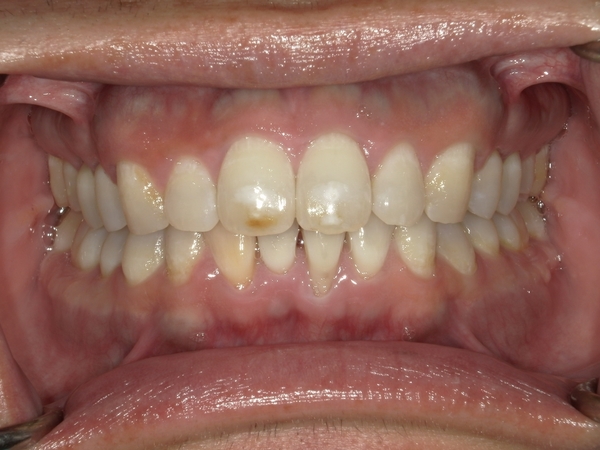

ガタガタとした歯並びや八重歯(叢生)CASE74